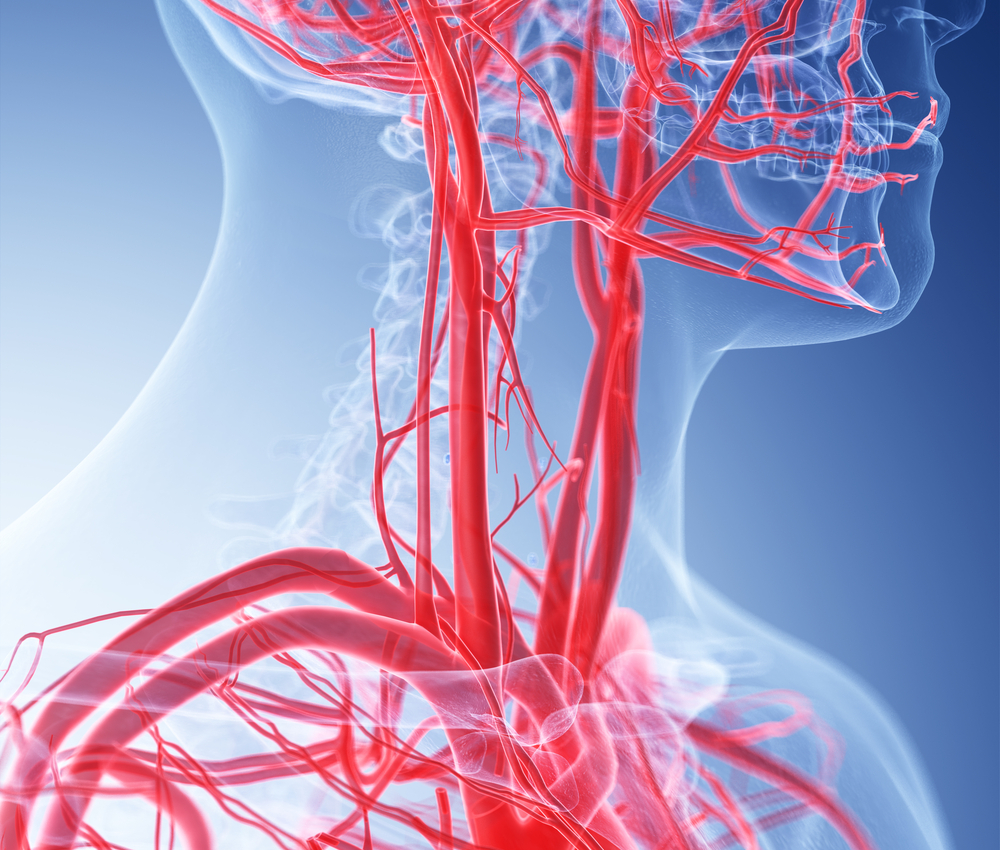

Кровеносная система человека: структура и функции

Раздел: Идеи и советы